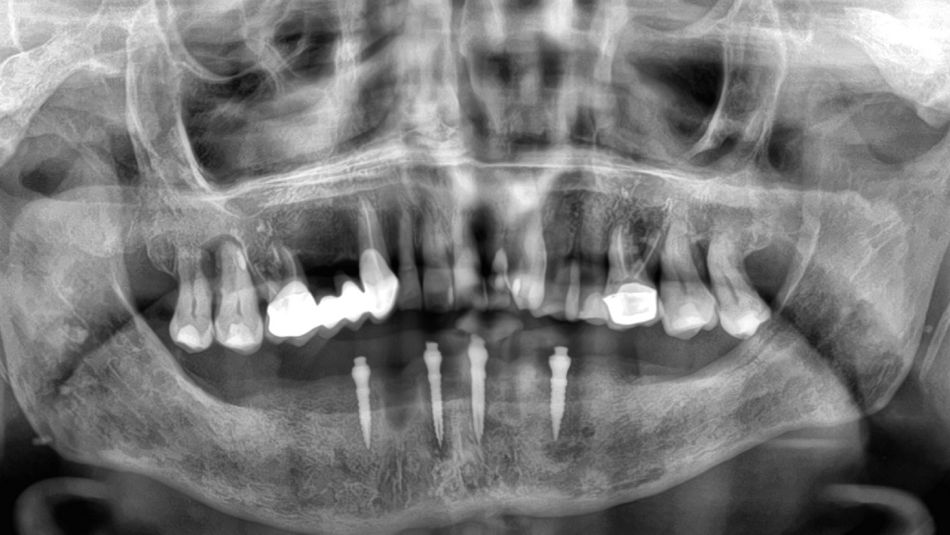

1a. 1b. Pre-operative panoramic X-ray and CBCT showing moderate generalised bone resorption in the mandible, a reduction in vertical dimension in the posterior region and the planned positioning of mini- implants.

1a

1b